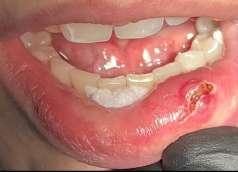

Il mucocele del cavo orale è la seconda lesione più comune. Nella fascia di età compresa tra 10 e 29 anni, il tasso di incidenza è più elevato. Il mucocele è caratterizzato da un accumulo di mucine. Ha una forma a cupola. Di solito hanno un colore bluastro. Il

mucocele si trova più comunemente sul labbro inferiore, seguito dalla mucosa buccale e dal pavimento della bocca. L'incisione tradizionale con bisturi e/o l'escissione chirurgica, la marsupializzazione, la micromarsupializzazione, l'iniezione di corticosteroidi, l'agente sclerosante, la criochirurgia, l'elettrochirurgia e il laser sono tutte procedure validate per il trattamento del mucocele in letteratura.

I laser a diodi forniscono una guarigione delle ferite e un tasso di recupero più rapidi rispetto ai loro rivali. Grazie alle sue

qualità antibatteriche e antinfiammatorie, questa terapia laser ha l'ulteriore vantaggio di migliorare la guarigione delle ferite senza infezioni o edema.

Le procedure laser-assistite sui tessuti molli presentano i vantaggi di un minimo sanguinamento intraoperatorio, edema e dolore postoperatorio, oltre a tempi chirurgici, cicatrici e coagulazione minimi.

Questo caso è coerente con precedenti segnalazioni di escissione del mucocele utilizzando un laser a diodi.

L'enorme quantità di tessuto rimosso e il livello di comfort del paziente supportano ulteriormente il fatto innovativo che può essere utilizzato anche per il mucocele di grandi dimensioni.

I mucoceli della mucosa orale sono malattie tumorali benigne delle ghiandole salivari minori della mucosa orale. Si verificano più comunemente nella mucosa labiale. Possono essere causate da una rottura dell'epitelio della ghiandola che secerne saliva nello spazio extraghiandolare e forma una pseudocisti (mucoceli da stravaso) oppure da un blocco del flusso salivare dovuto ad una proliferazione epiteliale del dotto escretore che forma una cisti salivare (cisti da ritenzione).